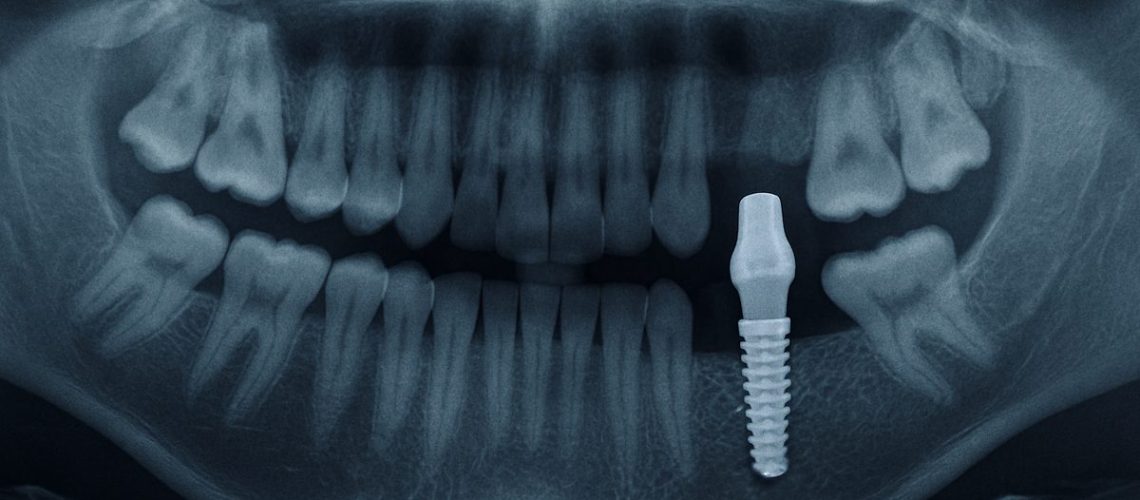

Image of a mouth x-ray showing a dental implant in the lower jaw, with an emphasis on the implant integrating with the jaw bone. No text on the image.

A dental implant is a small titanium post placed into the jaw to act as a tooth root. After the bone fuses to the post, a crown or denture attaches to it. The implant post and the crown are separate components: the post supports the tooth, and the crown resembles the visible tooth. Unlike bridges or removable dentures, implants replace the root and preserve bone, so they feel and function more like natural teeth.